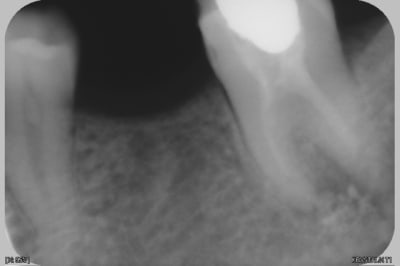

voila le cas

le patient est fluocalcique, en antagoniste im ya toutes les dents...

le patient est bien convaincu de la necessité de l'implant...mais je me dis, si je fais l'extraction illico, il faut voir l'ampleur de la resorption crestale qu'on peut avoir apres 5 ans...et penser à lui dire alors, ok tes economies pour l'implant ne suffiront que pour le rehaussement de la crete..